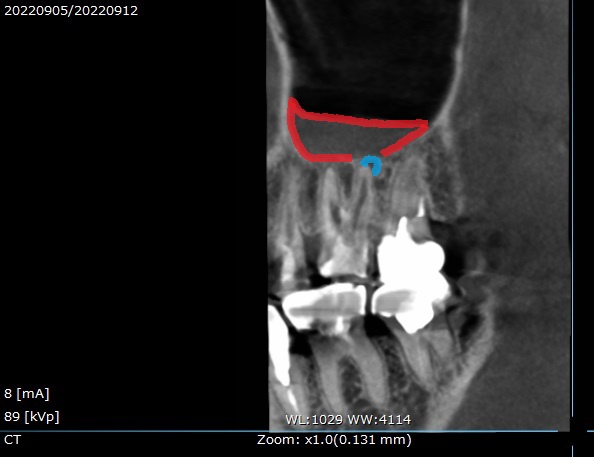

・治療1年後の状態

検診で来院された1年後に、新しくCTを撮影し状態を確認します。

1年後のCTの画像です。

正面からと、

横側からです☟

上顎洞の影が無くなっているのが分かります。

治療前と後の術前術後を比較してみましょう。

左上に撮影日の表示がありますが、

昨年2022年9月と、今年2023年9月のCT撮影です。

横側からの見た状態と、

正面からの状態。

矢印の場所の上顎洞の炎症が無くなり、本来の全体的に黒い空洞に戻っています。

治っていますね。

治療後のレントゲン写真では、根管にMTAセメントで充填してあり、

CTでは根の先まで白い詰め物がされているのが分かります。